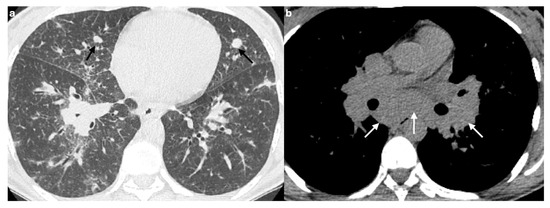

The Role of High-Resolution Lung Computed Tomography to Distinguish Between Fibrosing Hypersensitivity Pneumonitis and Usual Interstitial Pneumonia

Background: Hypersensitivity pneumonitis (HP) is an interstitial lung disease (ILD) caused by repeated exposure to inhaled antigens in susceptible subjects. High-resolution computed tomography (HRCT) of the lungs is the leading diagnostic method for ILDs, but in some cases HRCT findings are not sufficient to distinguish HP and other ILDs, particularly, fibrotic HP (fHP) and usual interstitial pneumonia (UIP). Objective: The aim of this study was to develop HRCT criteria to diagnose fHP in patients with a UIP-like pattern. Methods: In this retrospective study, we analyzed HRCT scans of patients with fHP and a UIP-like pattern who underwent lung biopsy, and patients with idiopathic pulmonary fibrosis (IPF) and a UIP pattern in HRCT. Results: We included 51 patients with confirmed fHP and 24 patients with IPF/UIP in the analysis. IPF/UIP patients were older, were prevalently males, and did not have any systemic autoimmune diseases or risk factors for other ILDs. fHP patients were younger, with an equal number of males and females, and were more likely to be exposed to environmental antigens. HRCT abnormalities in the fHP group predominated in the lower lung areas or were diffuse in axial scans, whereas IPF/UIP patients mostly demonstrated a diffuse craniocaudal distribution and subpleural axial predominance. Centrilobular nodules and mosaic attenuation were present significantly more often in the fHP group; honeycombing, traction bronchiectasis, and emphysema prevailed in IPF/UIP patients. In the logistic regression analysis, patients with fHP and IPF/UIP differed in the presence of centrilobular nodules, honeycombing, and in both craniocaudal and axial distributions of HRCT abnormalities. In the ROC analysis, the combination of centrilobular nodules, honeycombing, and diffuse axial and craniocaudal distributions can predict the diagnosis of fHP (AUC, 0.953 ± 0.022; 95%CI, 0.910–0.995; p < 0.001). Mosaic attenuation and reticulation did not change the probability of fHP. Conclusions: The most significant HRCT features of fHP compared to the UIP pattern were centrilobular nodules, honeycombing, and a diffuse axial and craniocaudal distribution of abnormal findings. Reticulation, mosaic attenuation, and GGO do not increase the probability of fHP. Full article

Figure 1